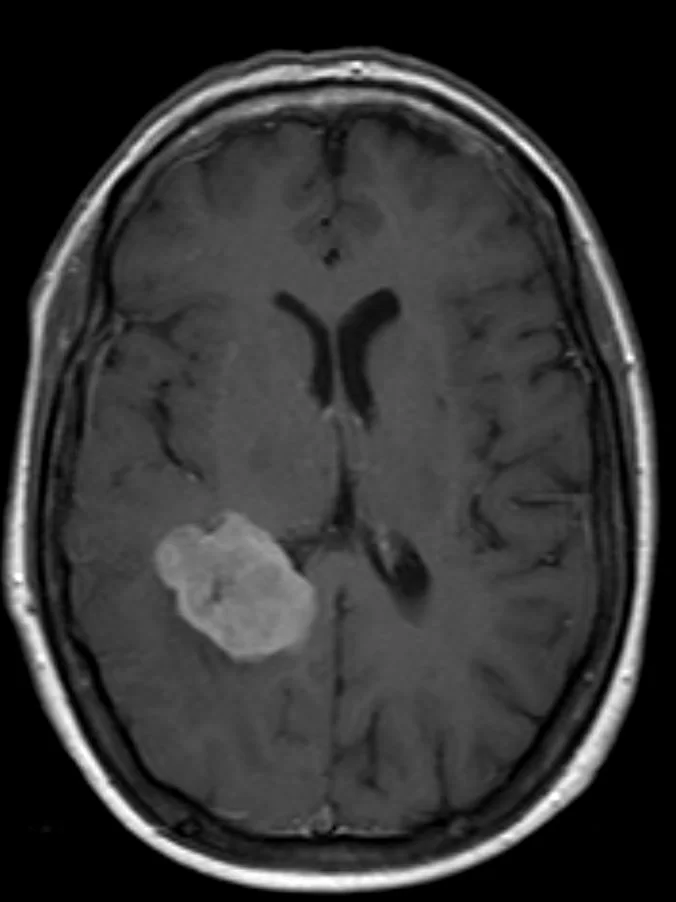

Ενδοκοιλιακό Μηνιγγίωμα

Ασθενής άνδρας, 49 ετών με επίμονες κεφαλαλγίες και τον τελευταίο καιρό και διαταραχές όρασης αριστερά. Η μαγνητική τομογραφία ανέδειξε χωροκατακτητική

Περισσότερα